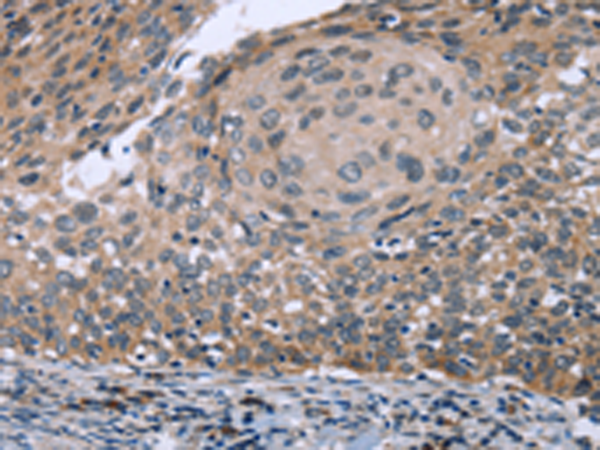

分类: 科研抗体货号: P08443别名:应用: IHC反应种属: Human, Mouse, Rat